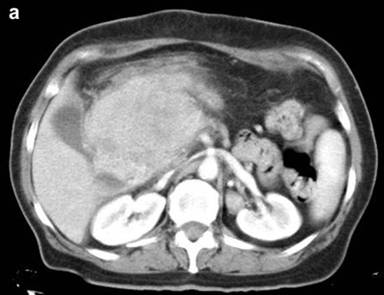

Abdominal CT scan (Figure 1ab) revealed a solid 12x10x8 cm polylobulated neoformative mass, slightly heterogeneous, involving the head of the pancreas without any fatty plane in between and in contact with the duodenum, portal vein, superior mesenteric artery and common hepatic artery.

Figure 1. Abdominal enhanced CT showing a large retroperitoneal mass involving the pancreas, the whole hepatic hilum and superior mesenteric vessels (a.). Some necrotic hypodense areas can be seen inside the mass (b.). |

The radiological features of inflammatory pseudotumor are usually not specific and normally appear as well-delimited and well-vascularized solid tumors, with a variable infiltrative appearance. They can reach a large size including necrotic hypodense areas [3, 4, 5, 14].